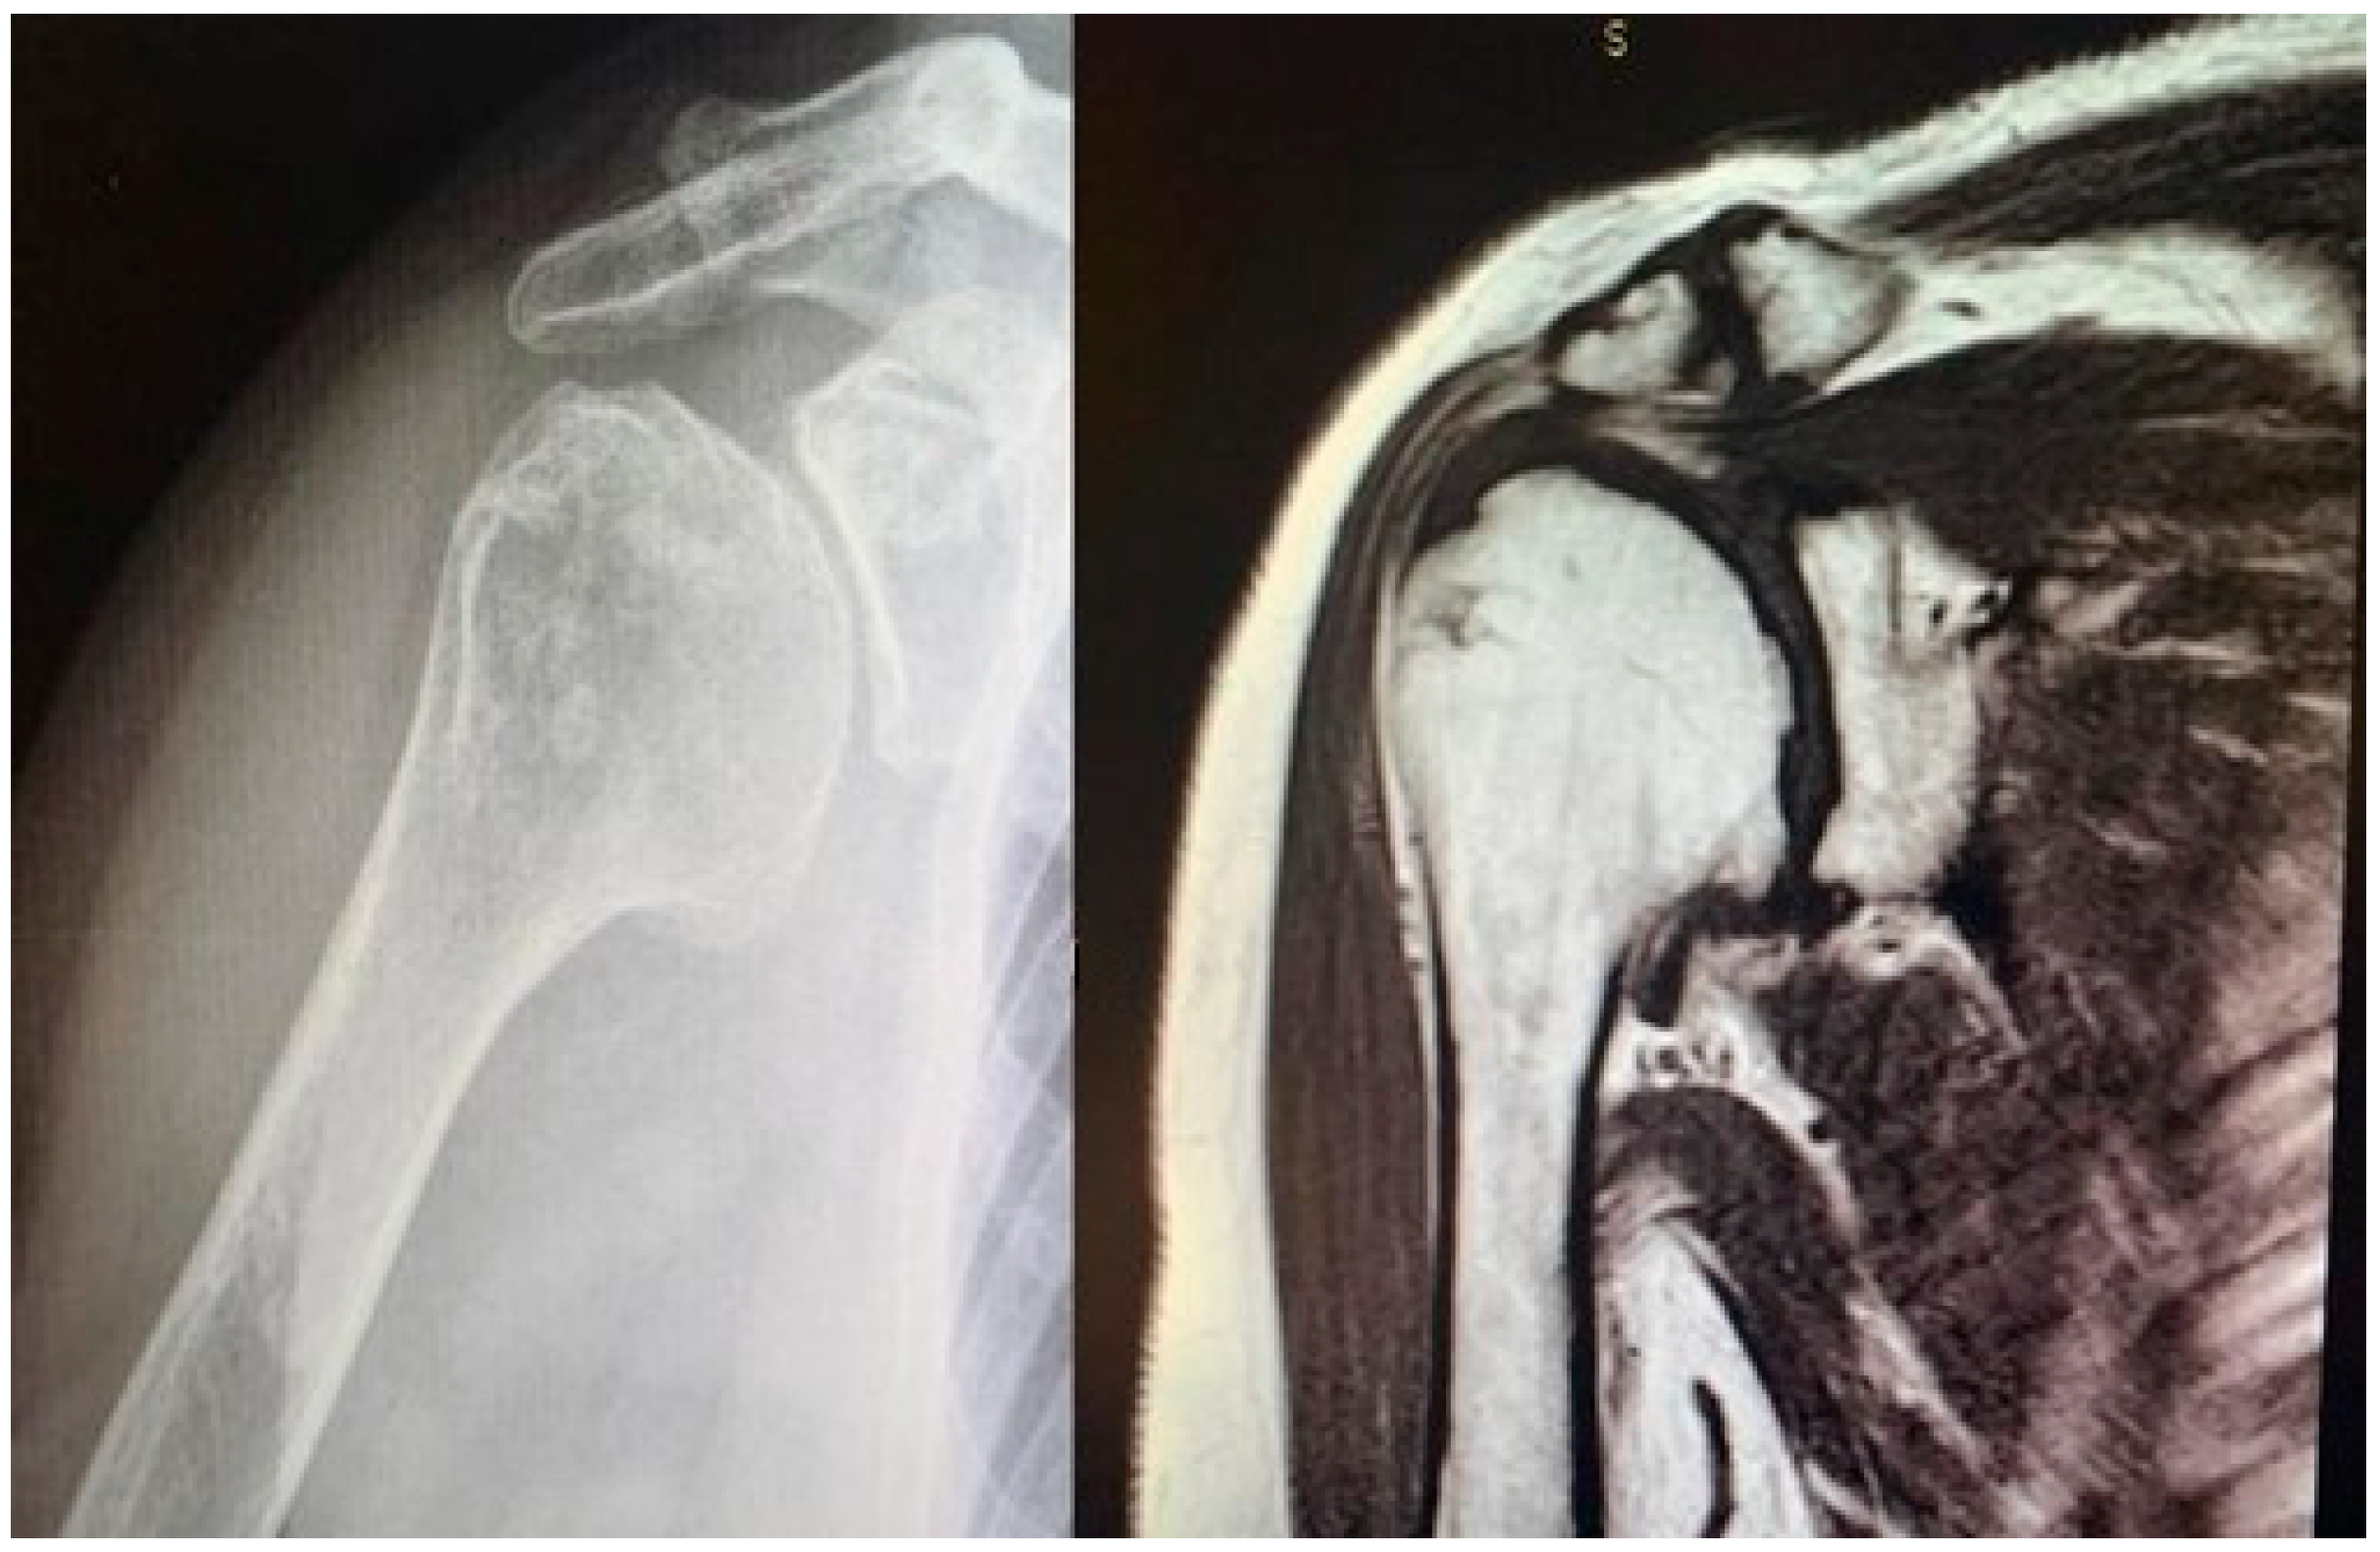

Study design. A retrospective and observational study was performed. The inclusion criteria were as follows: patients with (1) a diagnosis of glenohumeral degeneration with rotator cuff integrity following primary osteoarthritis (Figure 1) or rheumatoid arthritis or avascular necrosis of the humeral head, (2) glenoid articular surface type A1 or A2, according to Walch’s classification [17,18], (3) more than 60% residual humeral head [4,12], (4) who underwent HRA (Figure 2) operated on by a single surgeon and (5) who completed a minimum clinical and radiological follow-up of 2 years.

Figure 1. Concentric glenohumeral osteoarthritis.

Figure 3. Pre-operative magnetic resonance imaging to evaluate the integrity of the rotator cuff and the correct indication for an HRA.